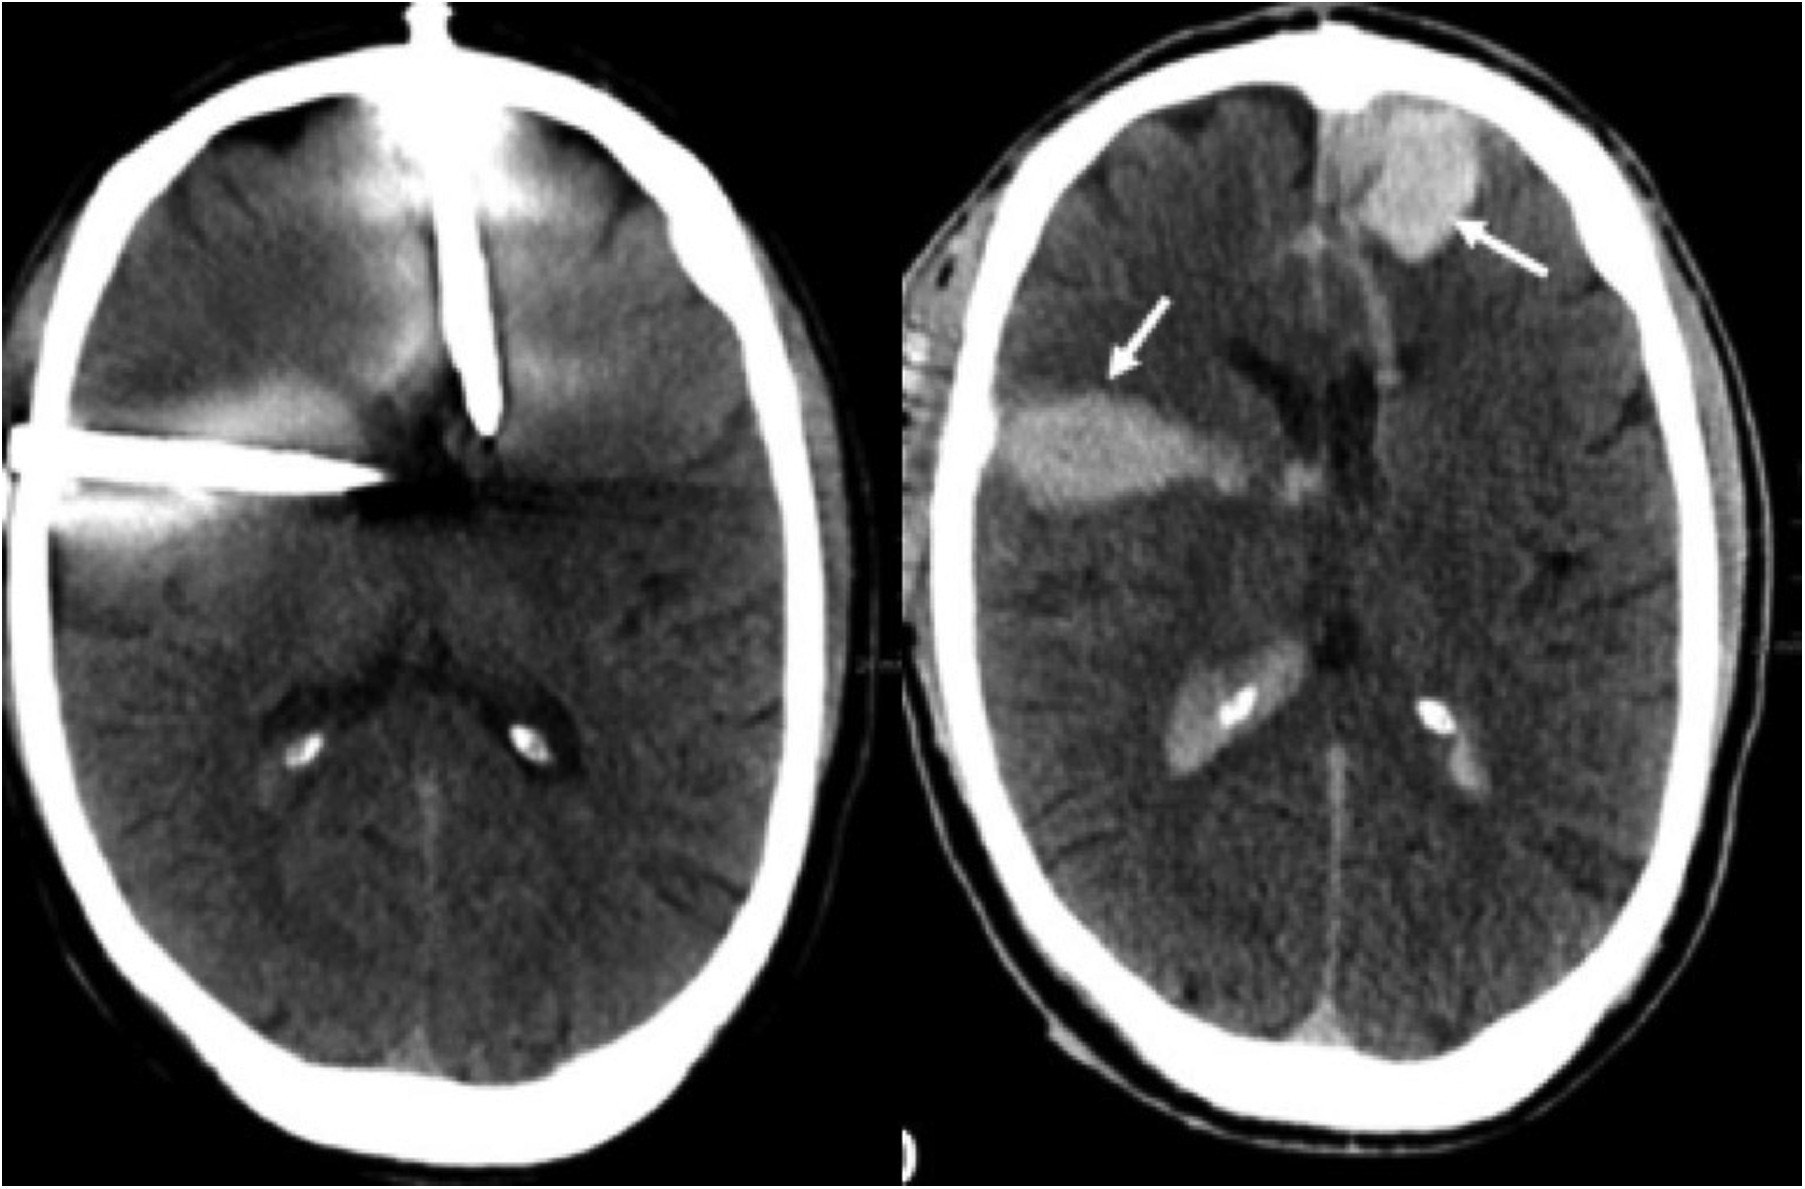

Following removal of the nails from the head, decision was made to observe the situation for a short interval. Cerebral CT-scan was repeated and showed a slight increase of the hematoma in the left frontal and right temporal regions (Figure 3). Since echocardiography did not show any increase of pericardial effusion, the patient was transferred to the intensive care unit and reassessed 2 and 4 h later. There, during careful removal of the clothes that had been transfixed by the nails, the patient's condition suddenly deteriorated very rapidly and echocardiography showed pericardial tamponade. Because of circulatory collapse, mechanical resuscitation would have been necessary but chest compression was not possible because of the nails still in situ. For this reason, emergency left thoracotomy was performed on the intensive care unit but adequate manual cardiac massage was not possible with the nails still in situ.

Figure 3. Cranial CT-scan before removal of the nails from the skull (left) with discrete bleeding and after removal with a progressive hematoma (arrow) (right).